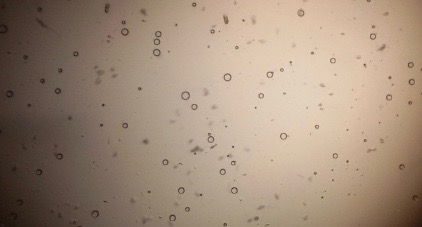

Proniosomes were transformed to noisome by hydrating with 10 ml distilled water at 37 °C and gentle agitation using vortex mixer (MaxiMix II, USA) for 5 min. The formed niosomes were sonicated twice for 30 seconds using sonicator (SONICS VCX 130, USA) [25]. The niosomal dispersion was put on a glass slide, and the formed vesicles were observed at a magnification of 1000x through an optical microscope. The formation of vesicles was observed using an optical microscope and photomicrographs were recorded [26].

The optical photographs of all reconstituted proniosomal formulae are shown in fig. (1-28). The photographs revealed that the formed niosomes are unilamellar vesicles with a spherical shape and smooth surface. The vesicles were insular and separate without aggregation or lumping. Apparently, proniosomal formulae containing span 40 and span 60 yielded vesicles of large numbers with well-identified outline and core which will affect the entrapment efficiency of loaded drug directly. However proniosomal formulae containing span 20 and span 80 produced small numbers of vesicles with a slightly different outline. This may be due to the high phase transition temperatures of both span 40 and span 60 which will cause the formation of a large number of stable niosomal vesicles. The phase transition temperatures for span 20, 40 and 60 are 16, 42 and 53 °C; respectively, however, span 80 possess the lowest phase transition temperature at 12 °C [35]. This explains why proniosomal formulae containing span 20 and span 80 produce small numbers of vesicles upon hydration.